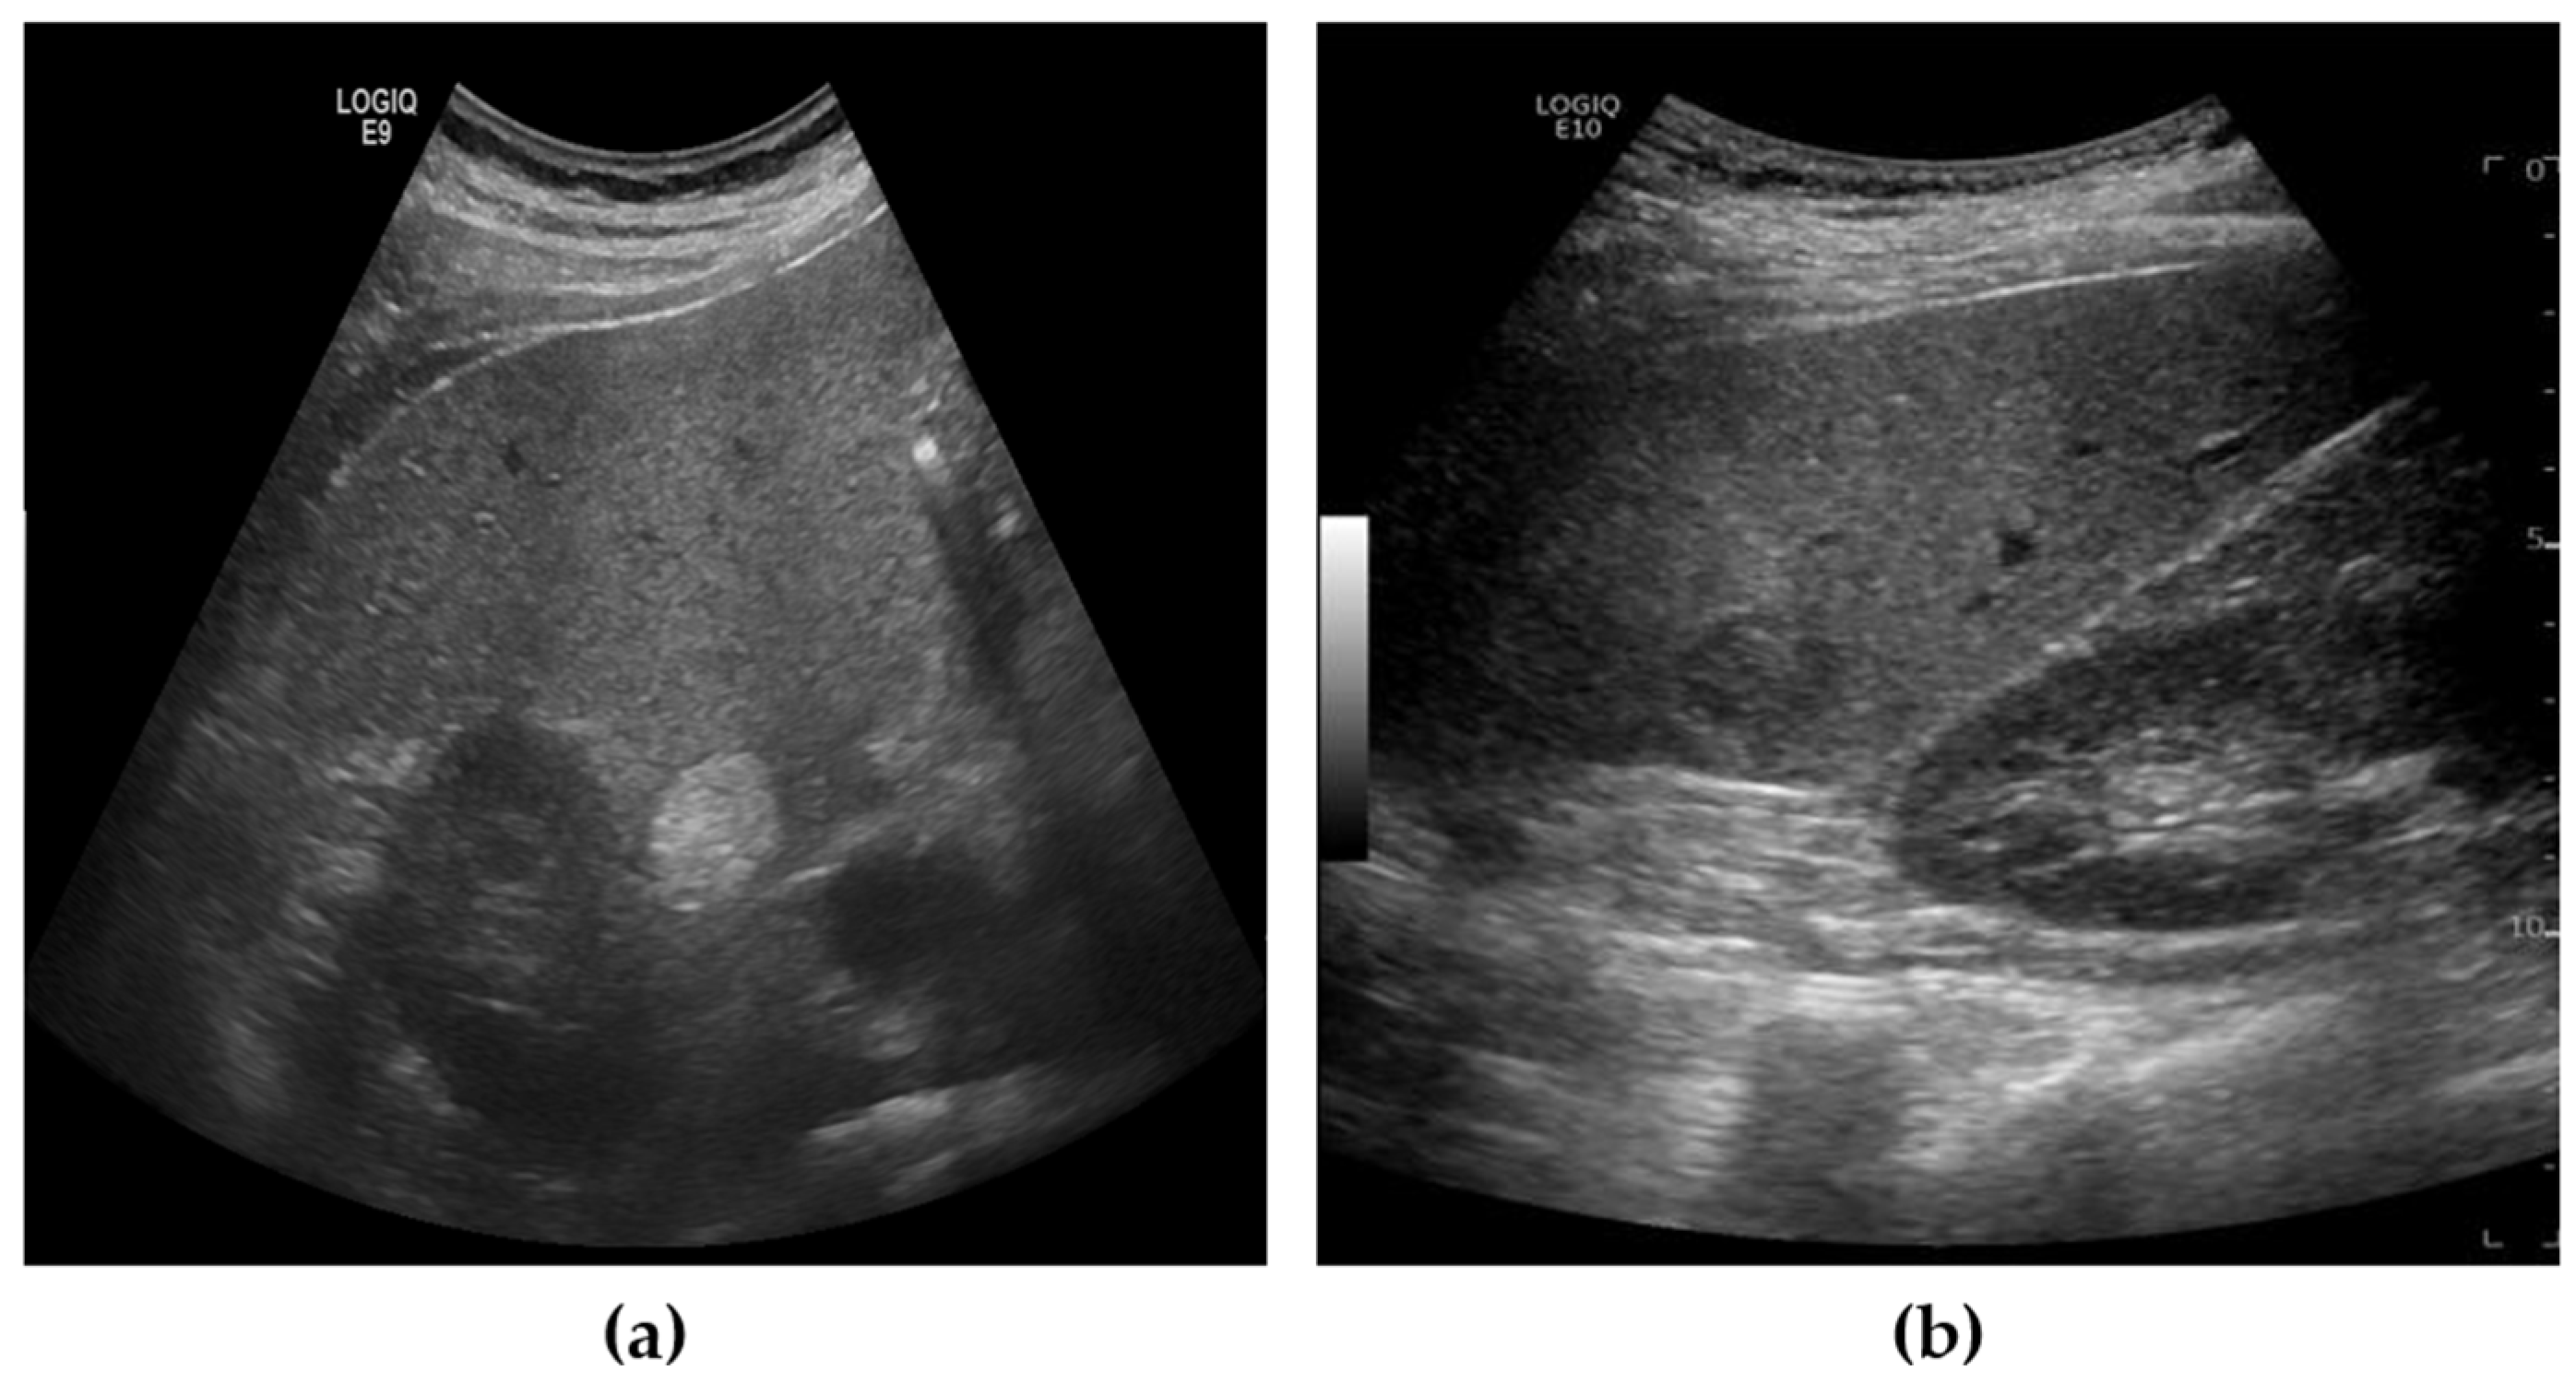

The liver US images used in this study were acquired using the Siemens ACUSON Sequoia 512 system (Siemens Healthineers, Erlangen, Germany), which operates at a frequency range of 3 to6 MHz, with 256 gray levels and a maximum depth of 36 cm. These images were collected under data use agreements and approved by the Institutional Review Board (IRB) of SMC, one of South Korea’s leading hospitals (SMC-2020-10-178-002). The dataset was annotated with two categories: benign and malignant. Since accurate diagnosis using only US images is challenging, the final labels were determined by SMC’s expert physicians after completing all necessary diagnostic procedures, including CT, MRI, and biopsy. The annotation for each patient’s US images was based on these comprehensive findings. Given the goal of our study to develop a screening tool, lesions were categorized simply into benign or malignant, rather than employing more granular labeling. Figure 1 provides examples of benign and malignant cases from our dataset.

Figure 1.

Example of US images from dataset. (a) Benign, (b) Malignant.

The dataset consisted of a total of 1054 ultrasound images, collected from patients aged 48 to 82 years. Among these, 746 images were labeled as benign, and 308 images were labeled as malignant. For model development and evaluation, the dataset was divided into training, validation, and test sets in a 6:2:2 ratio.